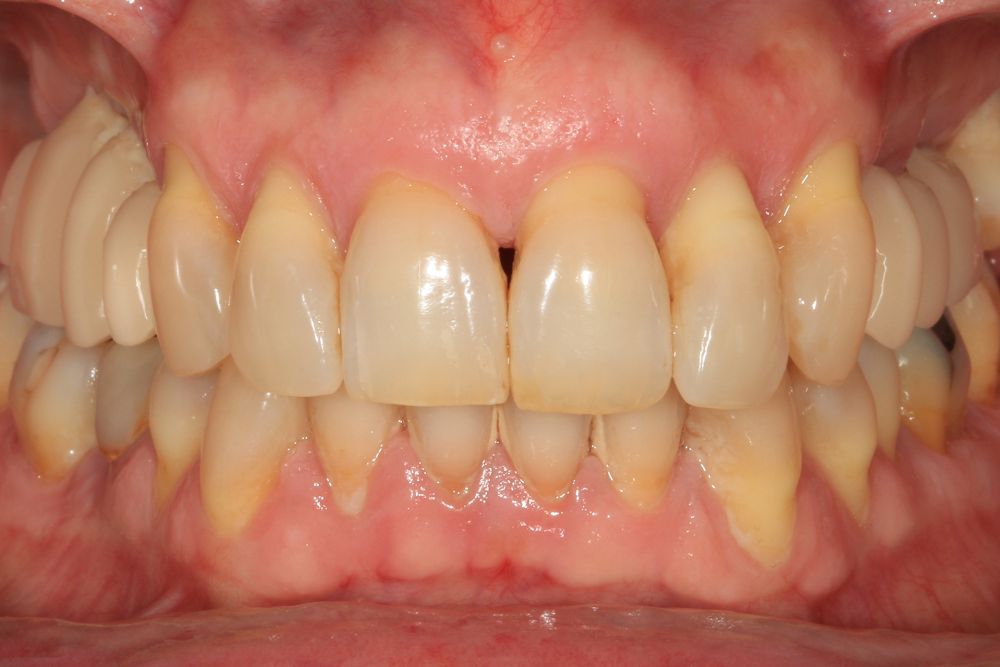

Presentamos el caso de una paciente femenina de 56 años de edad que acude a la consulta demandando un tratamiento con implantes dentales para reponer los dientes ausentes en ambos sectores posteriores maxilares. En ambos cuadrantes superiores, los molares se perdieron hace varios años. La paciente no se ha realizado la reposición de los mismos hasta ahora, ya que en otros centros consultados la propuesta terapéutica fue la de realizar injertos y regeneración ósea para poder ganar volumen óseo suficiente antes de colocar los implantes. La paciente busca otras alternativas menos invasivas y por ello acude a la visita. En las imágenes intraorales se observa la falta de los molares en los sectores posteriores maxilares con excepción del 27, que actualmente tiene un compromiso periodontal importante (Figuras 1-4). El resto de dientes también se encuentran afectados por una enfermedad periodontal avanzada con pérdida ósea horizontal (Figura 5).